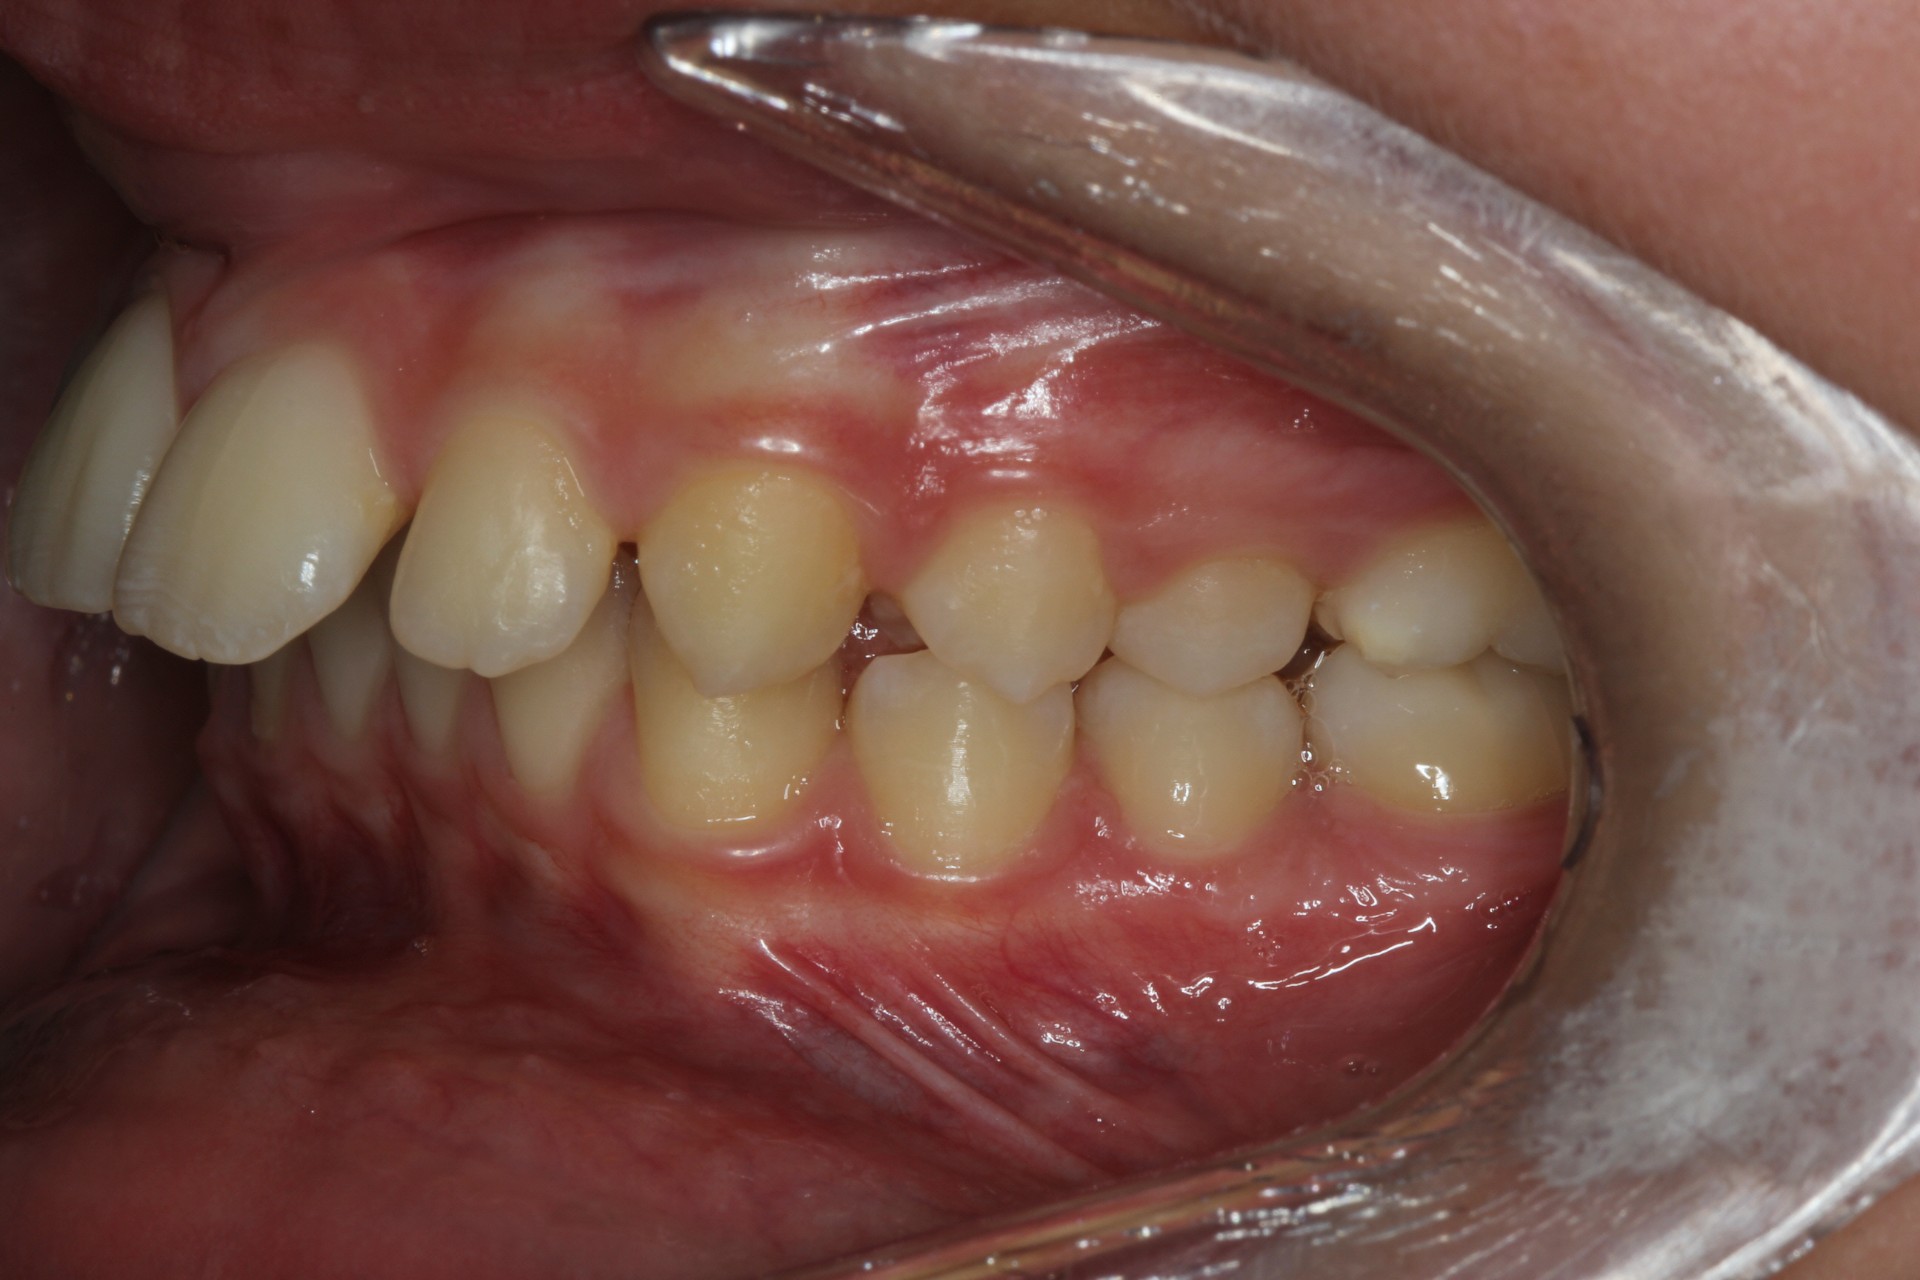

Protruding front teeth – Child case